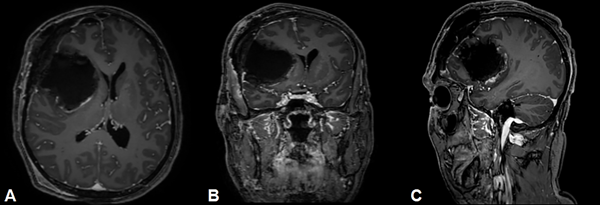

En estudio de resonancia magnética postquirúrgico a las 48 horas de la intervención en secuencias T1, T2, FLAIR, difusión (SWI) y T1 con gadolinio (Fig. 3) no se observaron signos de residuos tumorales.

Fig. 3. Resonancia magnética postquirúrgica, cortes axial, coronal y sagital en secuencia T1 con Gadolinio. Lecho quirúrgico sin lesión tumoral residual.